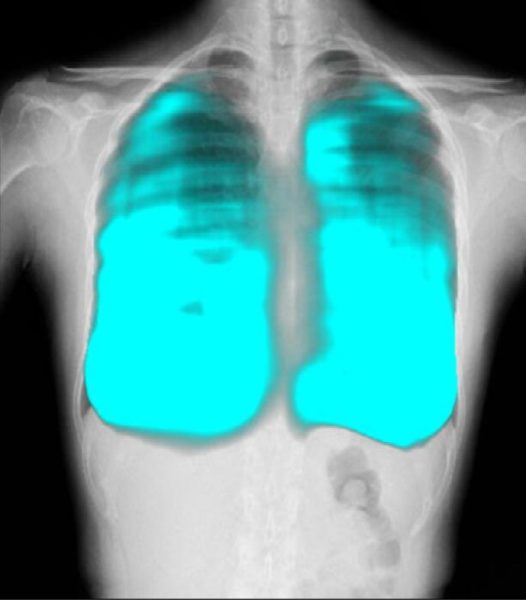

コニカミノルタのX線動態解析技術/イメージングAI技術と、FPTの高度なAI技術を活用し、呼吸器疾患の診断支援、医療レポートの自動生成など新しい診断技術の確立を目指す。コニカミノルタ独自の「X線動態解析」は、世界で300件以上の特許を取得しており、既に400台以上の販売実績がある。ベトナムの医療イノベーションとデジタル変革による呼吸器疾患対策を推進することで、国民の健康と医療従事者の負担軽減に貢献する。

簡易かつ高度なX線動態解析画像を用いた呼吸器疾患に関する医療指標の開発と、AI診断支援ツールの開発による呼吸器疾患の早期診断機会創出。

コニカミノルタはデジタルX線動態撮影および動態解析を、新しい“動きの診断”を提供するソリューションとして展開している。この同社独自の技術「X線動態解析」を搭載したシステムとして、一般X線撮影装置を用いて動画を撮影できるデジタルX線動態撮影システムを開発・提供しており、既に国内外の医療機関で導入実績がある。